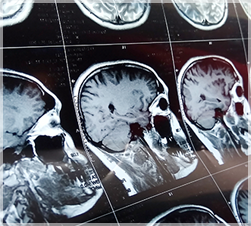

Minutes matter during a stroke. The faster you are diagnosed and treated, the better the chances for recovery. Riverside offers a network of expert stroke specialists and advanced stroke treatments. A Riverside certified stroke center is near you and ready to treat any kind of stroke or stroke complication, anytime, day or night. Riverside's stroke centers adhere to the highest standards of care – to rapidly and accurately diagnose and apply advanced emergency stroke treatment.